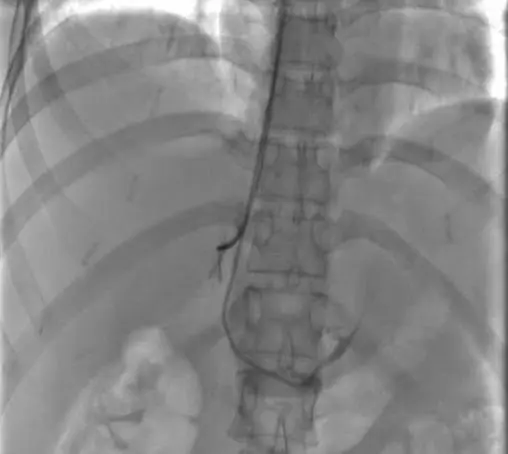

术中双侧肾上腺静脉同时造影

在心脏起搏介入治疗中心导管室,谢翔教授通过在患者的右上肢肘正中静脉同时植入2根鞘管,分别送2根导管至左、右肾上腺静脉,经造影证实插管成功。导管到位后同步进行取血、送检。手术过程约30分钟,术后拔出鞘管后局部加压包扎2小时,患者即可自行活动。